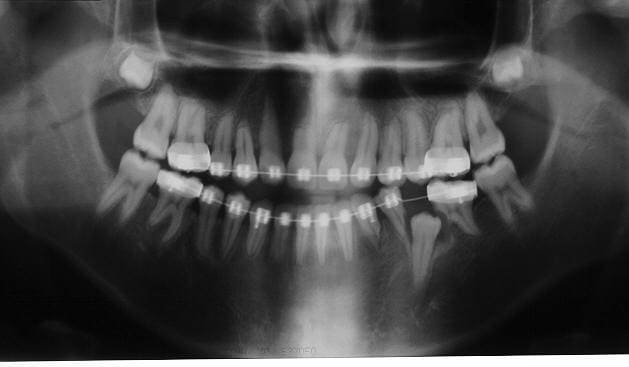

2 ptites rhisalyses...pour les 2 centrales sup, consécutif à un trauma dans l'enfance, l'ODF n'y est pour rien...

Pour l'autre cliché, ce sont les prémolaires qui ont bouffés les racines en évoluant...maintenant, y a un terrain parce que des rhisalyses y en a sur toutes les autres dents...

je recommence pour les clichés

Rhisalyse iomvob - Eugenol

Dep ir5umh - Eugenol

1 eugenol dmj5np - Eugenol